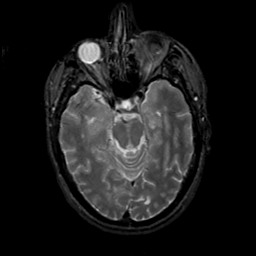

MR Study #19, August 25, 1991 -- Slice #18